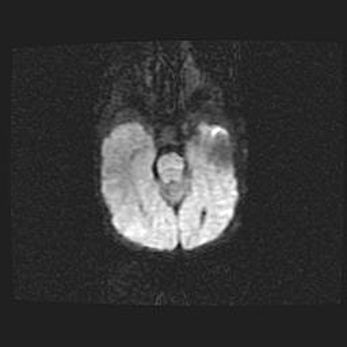

Подострая гематома правой гемисферы мозжечка.

Наружная гидроцефалия.

Возраст: 15 дней

Вес: 3100 г

Пол: женский

Окружность головы: 37 см

Срок гестации: 35-36 недель

При открытой наружной форме гидроцефалии у новорожденных расширяются и переполняются субарахноидные пространства.

Кровоизлияния в мозжечок имеют две клинико-анатомические формы: полушарные гематомы и кровоизлияния в червь.

К появлению этой патологии может привести: повреждения головного мозга, возникающие в результате асфиксии и гипоксии плода при беременности, или травмы во время родов. Редко гематома мозжечка может быть результатом первичной коагулопатии и сосудистой мальформации, диссеминированном внутрисосудистом свертывании, изоиммунной тромбоцитопении.